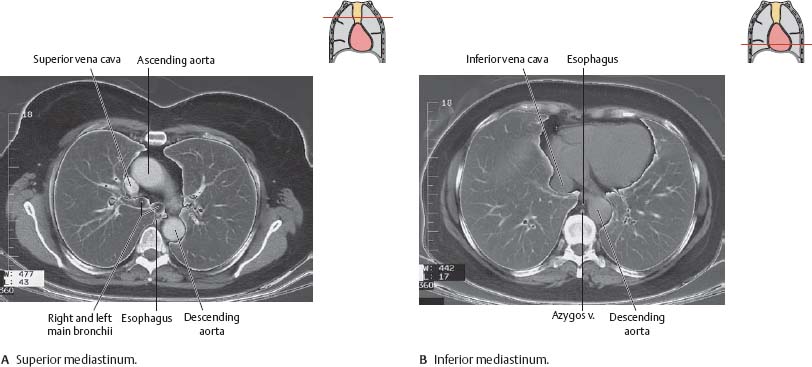

Fig. 6.3 Transverse sections of the thorax

Computed tomography (CT) scan of thorax, inferior view.